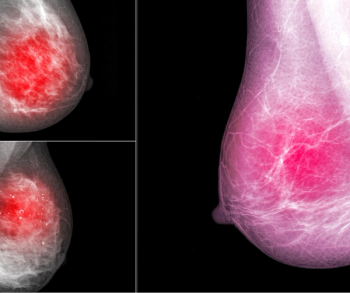

An artificial intelligence algorithm for dynamic contrast-enhanced breast MRI offered a 93.9 percent AUC for breast cancer detection, and a 92.3 percent sensitivity in BI-RADS 3 cases, according to new research presented at the Society for Breast Imaging (SBI) conference.

Artificial intelligence (AI) assessment of mammography images may significantly enhance the prediction of invasive breast cancer and ductal carcinoma in situ (DCIS) in women with breast cancer, according to new research presented at the Society for Breast Imaging (SBI) conference.

Adjunctive use of an artificial intelligence (AI) software demonstrated nearly equivalent sensitivity and over 28 percent higher accuracy in comparison to radiologist assessment of breast ultrasound images for breast lesions, according to new research presented at the recent Society of Breast Imaging (SBI) conference.